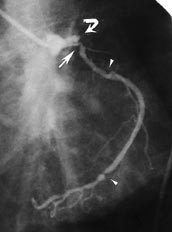

Pasient 3. 74 år gammel mann med kjent moderat nyresvikt. Tidligere fire hjerteinfarkter, og flere innleggelser i månedene før angiografien på grunn av ustabil angina pectoris og lett hjertesvikt. Etter behandling av hjertesvikt og stabilisering av angina pectoris ble koronar angiografi utført. Denne viste markert nedsatt funksjon av venstre ventrikkel, flere stenoser i venstre koronararteries ramus circumflexus, sentral lukning av ramus descendens anterior (fig 3) og av høyre koronararterie. Pasienten fikk smerter i brystet under siste del av undersøkelsen, og ble smertefri etter nitroglyserin sublingvalt og morfin intravenøst. Pasienten fikk stigning i CK-MB-nivå til 60 U/l, forenlig med et relativt lite hjerteinfarkt. I tillegg fikk pasienten abdominalsmerter etter angiografien. Kirurg fant ikke holdepunkter for mesenterial emboli/trombose. Pasienten ble likevel behandlet med heparin 5 000 IE ⋅ 2 subkutant. Ubehaget i øvre abdomen fortsatte i dagene etterpå, og pasienten utviklet et nytt hjerteinfarkt med største CK-MB-verdi på 134 U/l tre dager etter angiografien. Han fikk feber og stigning i CRP, og da røntgen thorax viste lungestuvning og mulig pneumoni, fikk han antibiotikabehandlig. Etter hvert fikk pasienten tiltakende multiorgansvikt, og han ble respiratorbehandlet fra dag 4 etter angiografien. Til tross for maksimal behandling, døde han 5. dag etter angiografien.